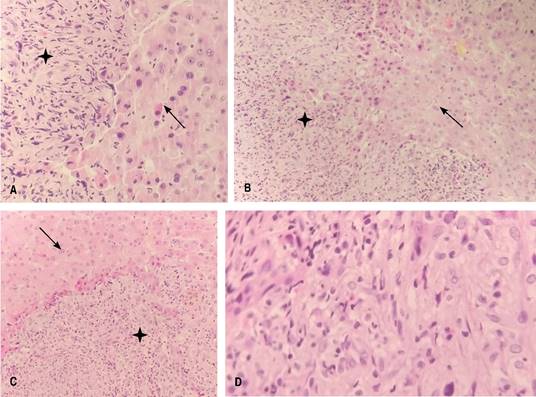

Reporte histopatológico de implante hepático: neoplasia maligna moderadamente diferenciada, consistente en carcinoma hepatocelular sarcomatoide (Figuras 4 y 5).

Figura 4: Se observan células hepáticas de aspecto neoplásico, las cuales muestran núcleos heterogéneos con nucléolos prominentes con citoplasma amplio eosinófilo. Estos grupos celulares en algunas áreas se intercalan con células fusiformes con atipia caracterizada por núcleos pleomórficos y mitosis atípicas (señalados con una flecha).

Figura 5: (A-C) Se observan células hepáticas neoplásicas (señaladas con asterisco) intercaladas con una neoplasia de células fusiformes (señaladas con flecha). Se puede observar la transición de los epitelios. (D) Células fusiformes típicas del CHCS.